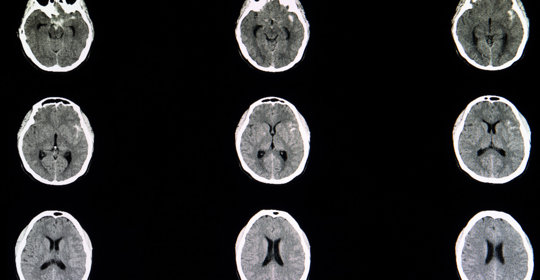

腦中風後遺症的症狀、前兆、治療和預防

腦震盪後遺症的症狀表現、前兆、治療與預防

腦溢血後遺症的症狀、前兆、治療和預防

腦血管破裂後遺症的症狀、前兆、治療和預防

腦梗塞後遺症的症狀、前兆、治療與預防

腦出血引流手術後遺症的症狀、前兆、治療和預防

腦栓塞後遺症的症狀表現、前兆、治療與預防

腦缺氧後遺症的症狀表現、前兆、治療及預防